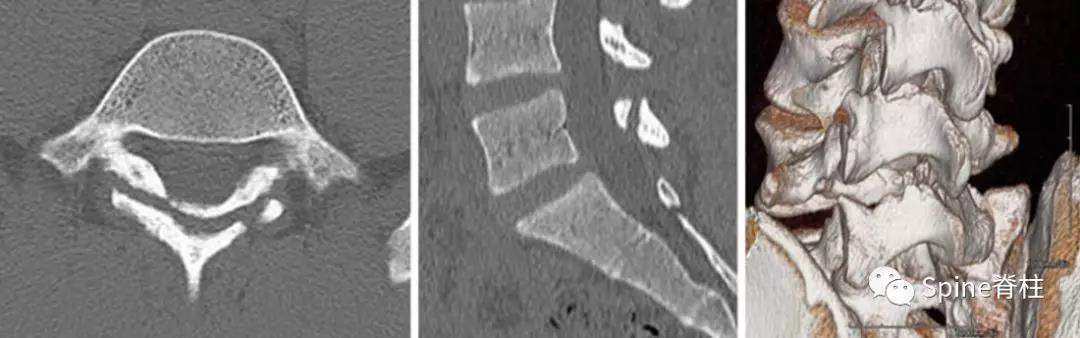

图:L5半椎板裂15岁篮球运动员,严重腰痛,影响睡眠CT示:左侧为椎板裂(箭头),右侧为峡部裂(箭头)